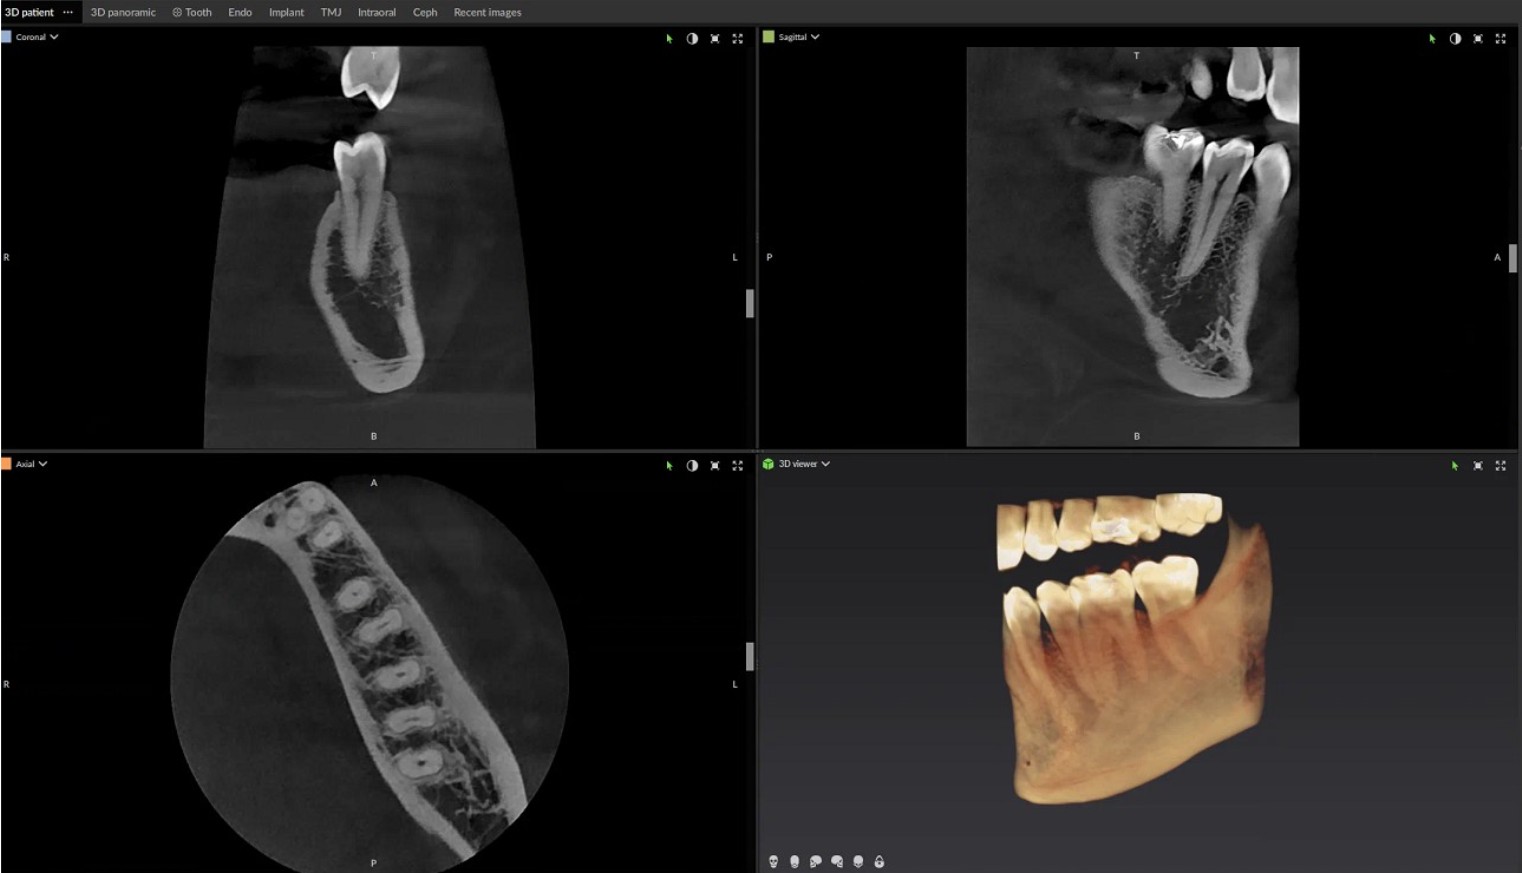

Below we see two images: the first is of a traditional radiograph with some pathology visible around the roots of an upper molar, and the second is an image showing 2D slices of pathology visible around the entire tooth and sinus.

The actual 3-D image can be manipulated to show any combination of slices so one can "move through the tooth" to check for potential issues.

Below are some 2D slices of a CBCT scan.